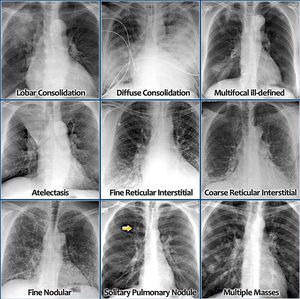

Chest X-ray interpretation

Lung

Pulmonary

Chestxray

Radiography